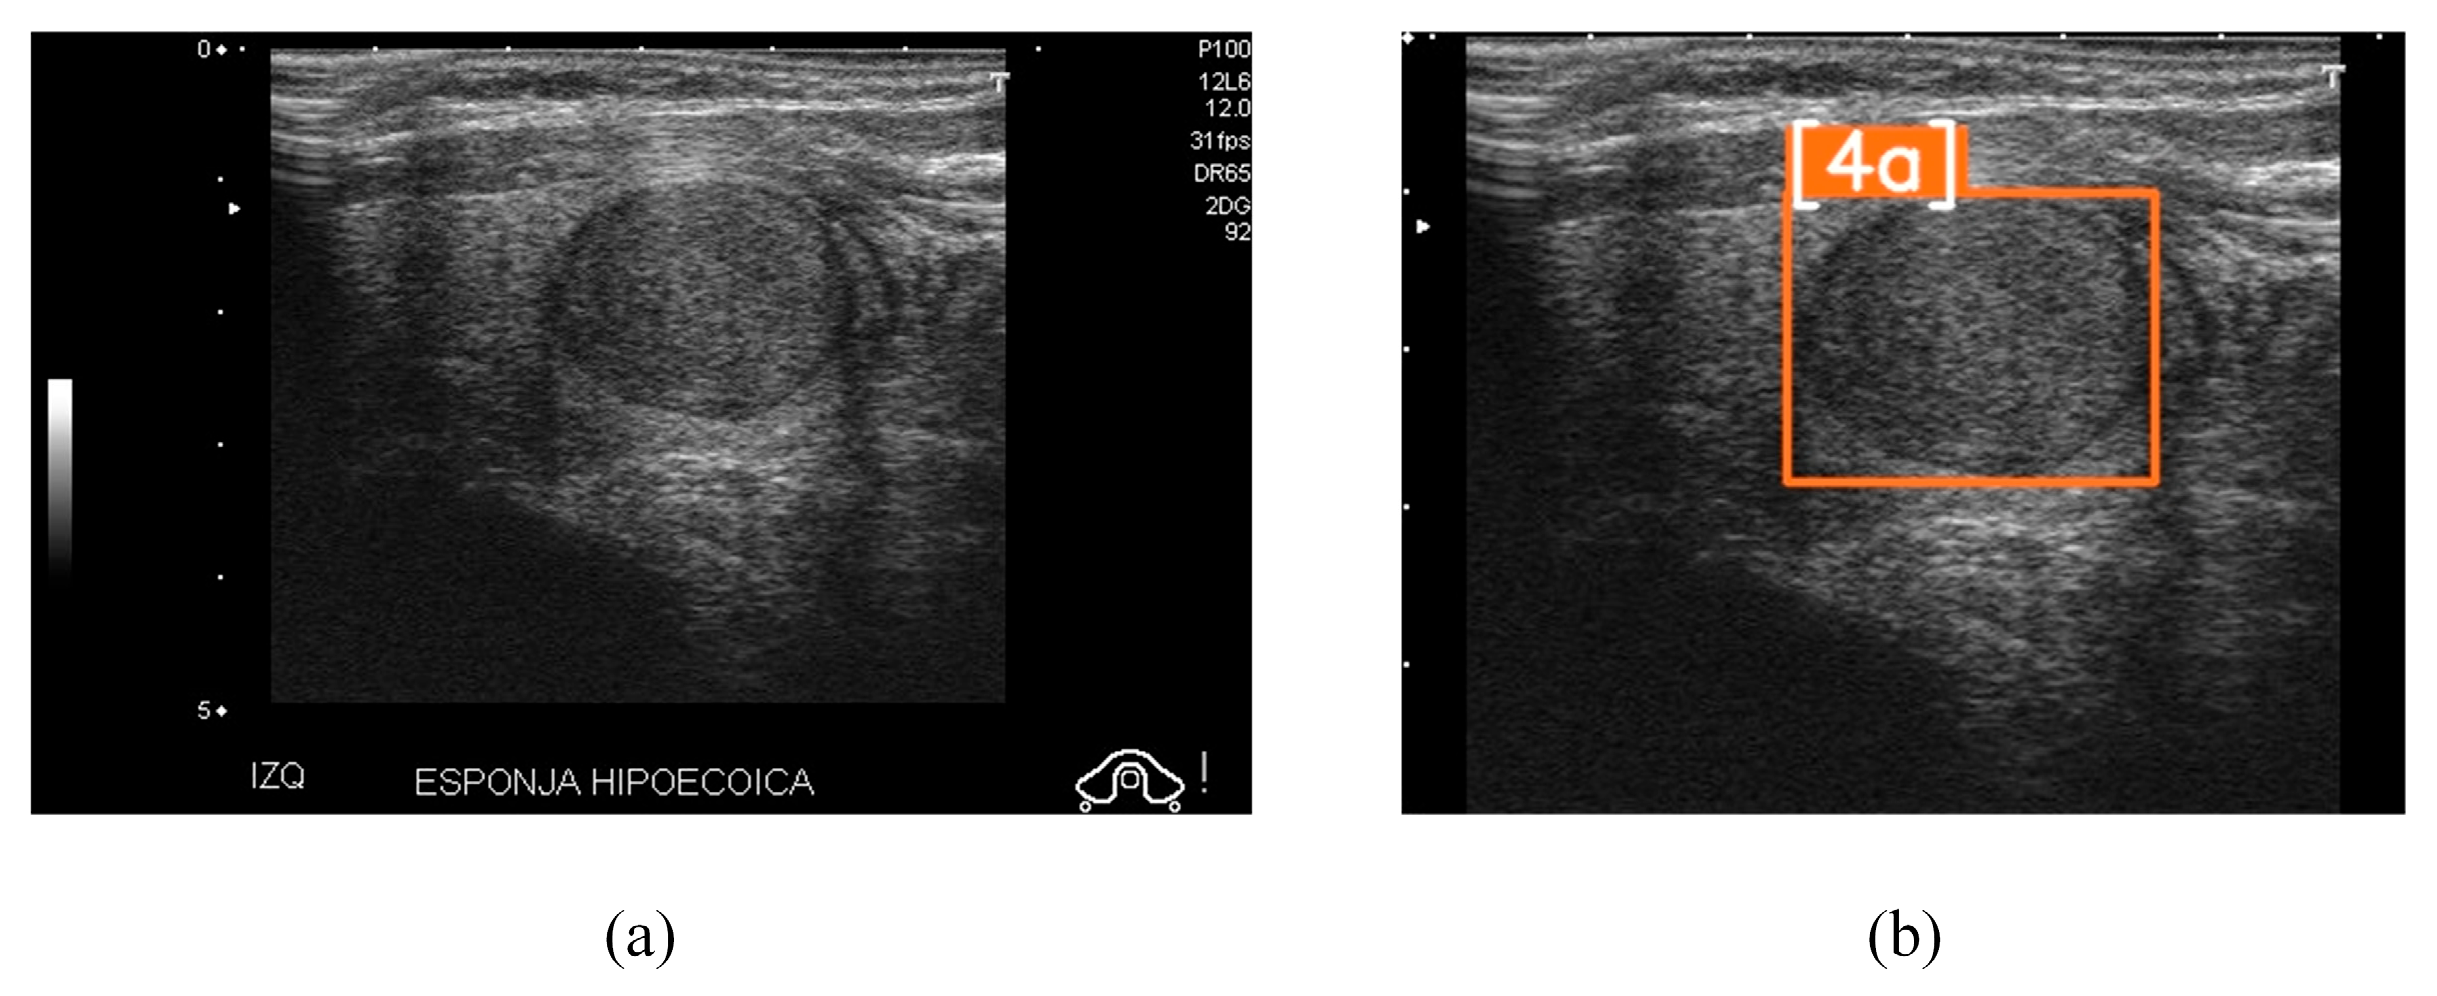

- [4a] One suspicious US feature (5–10% malignancy);